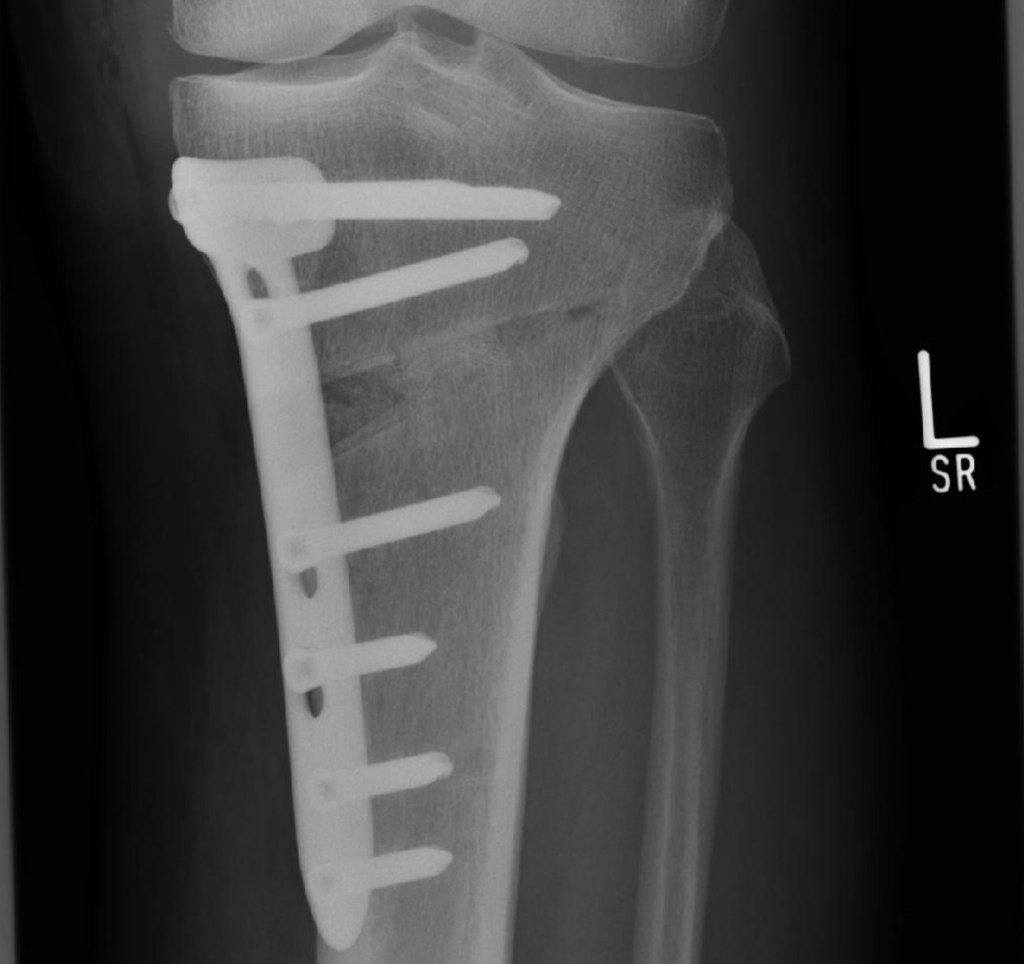

Die o. g. Frage haben sich bestimmt einige gestellt. Anhand der Zugriffszahlen in den letzten Wochen habe ich bemerkt, dass das Leben in meinem Blog scheinbar vermisst wird. Und es tut mir schon weh, dass ich momentan und auch in den nächsten Wochen nicht die Möglichkeit habe, sozusagen „fast live“ von den Barnimer Fußballplätzen zu berichten. Wer meinen Blog regelmäßig verfolgt, wird Anfang August diesen Eintrag (link) gelesen haben. Resultierend aus dieser Operation hat sich nun ein Folgeeingriff ergeben, der mich wiederholt in die Zwangspause gezwungen hat. Und diesmal noch deftiger als im August. Kurz erklärt, hat sich beim ersten Eingriff im Sommer ein Knorpelschaden vierten Grades im Innenbereich des Knies, gepaart mit einer Arthrose ergeben, welche eine Umstellungsosteotomie (HTO) des Knies durch eine Fehlstellung in der Beinachse erforderlich gemacht hat. Für Nichtmediziner einfach dargestellt: Ich hatte starke O-Beine und das Linke wurde nun begradigt. Hier sind drei Abbildungen, die einmal meine Beine im postoperativen Zustand zeigen und dazu zwei Fotos, auf denen zu sehen ist, was an meinem Unterschenkel gemacht wurde. Er ist „aufgekeilt“ worden und mit einer Metallplatte arretiert, so dass ich in Zukunft mehr mein Außenknie nutze, in dem noch einiges an Knorpelmaterial vorhanden ist. Klingt logisch, oder …?